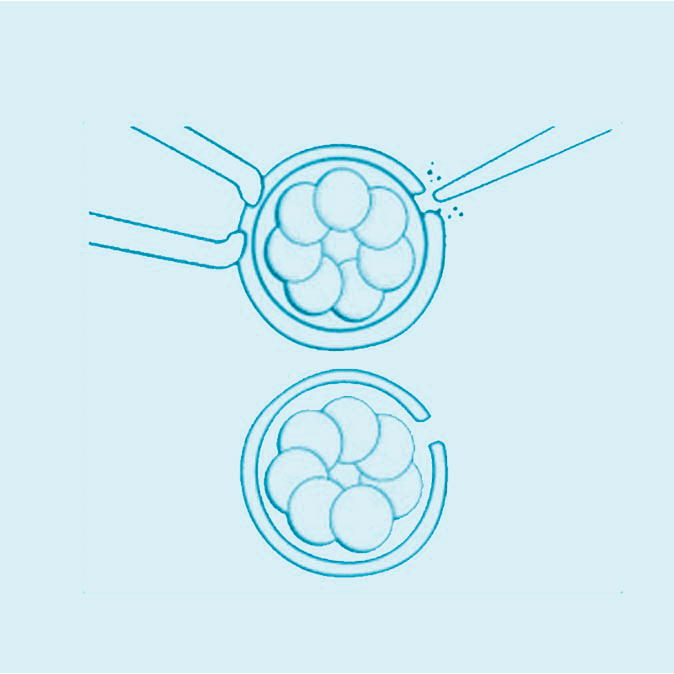

Eclosion Assistée

La référence

Nous mettons à la disposition de nos patients un bloc opératoire hautement équipé, dédié aux interventions de fertilité et aux techniques innovantes de chirurgie mini-invasive, garantissant précision, confort et récupération rapide. Notre laboratoire de biologie de la reproduction, doté d’équipements de pointe, assure toutes les étapes essentielles : fécondation in vitro (FIV), ICSI, congélation d’ovocytes et d’embryons, diagnostic embryonnaire, optimisation de la qualité ovocytaire et spermatique… Chaque procédure est réalisée selon les standards internationaux afin d’assurer les meilleures chances de réussite.